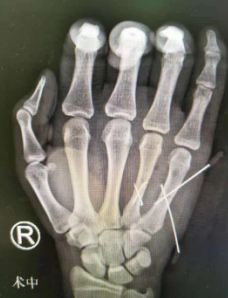

6月20日中考结束,强强和妈妈就再次来到了医院,并于当天下午进行了右手第4、5掌骨骨折切开复位内固定手术。手术非常顺利,术后第二天强强还用双手打起了游戏。

术后即刻